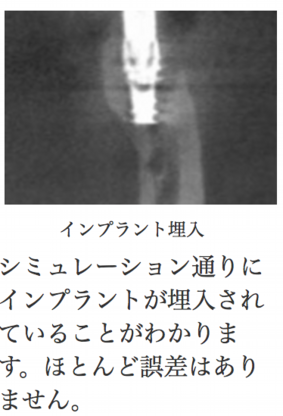

ドイツシロナ社はより安全なインプラント治療のためCMG(Cerec Meets Galileos セレックミーツガリレオス)という最新技術を生み出しました。CTは確かに優れていますが、今現在こまいかい所まではきれいに映りません。そこで、セレックによる3Dカメラのデータを取り込むことで、口の中とCTデータを融合させることにしました。そうすることで、最終補綴まで計算し、かつ骨の状態も把握できる最良の治療法が生まれたのです。

3Dカメラを使うセレックシステムとCTを3D解析できるガリレオスのデータを融合して、すべてコンピューターの中でインプラント埋入、アバットメントセット、かぶせのセットまでシミュレーションできてしまう、超先進技術です。まるで未来にきたように錯覚するかもしれません。これにより最終的な形が予測できる上、危険な治療ではないか、加えて必要な治療があるかどうかもわかります。